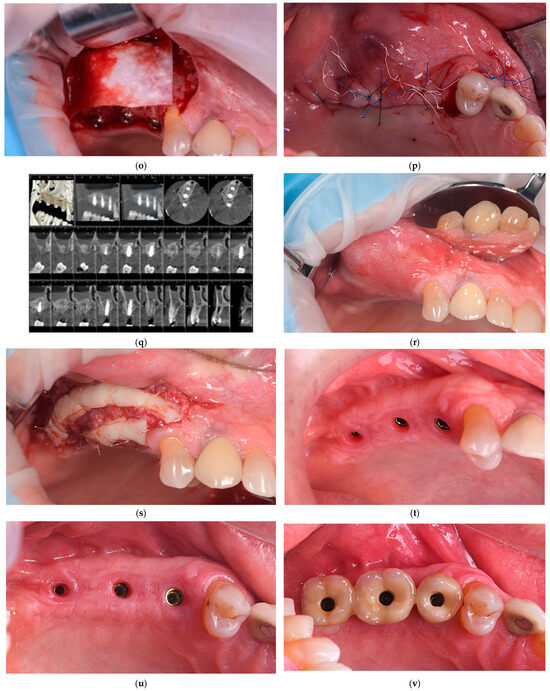

This Special Issue, “Innovations and Challenges in Dental Implantology”, seeks to highlight cutting-edge research and practical insights into key aspects of implantology. Topics of interest include advancements in osseointegration, biomaterials, autologous blood-derived products, and enhanced approaches to guided bone regeneration and bone augmentation. Contributions addressing sinus elevation techniques, peri-implantitis prevention and treatment, soft tissue management, and strategies to mitigate implant failures are highly encouraged. Furthermore, we welcome studies focusing on surgical or non-surgical salvage techniques, providing valuable insights into the management of complications in dental implantology.